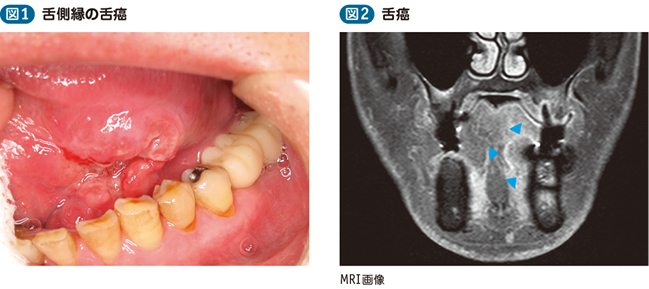

Chapter 2 頭頸部がんの検査と診断 頭頸部がん がん免疫 Jp Immuno

父の癌細胞が消滅したct Mri画像 難病 末期癌からの生還